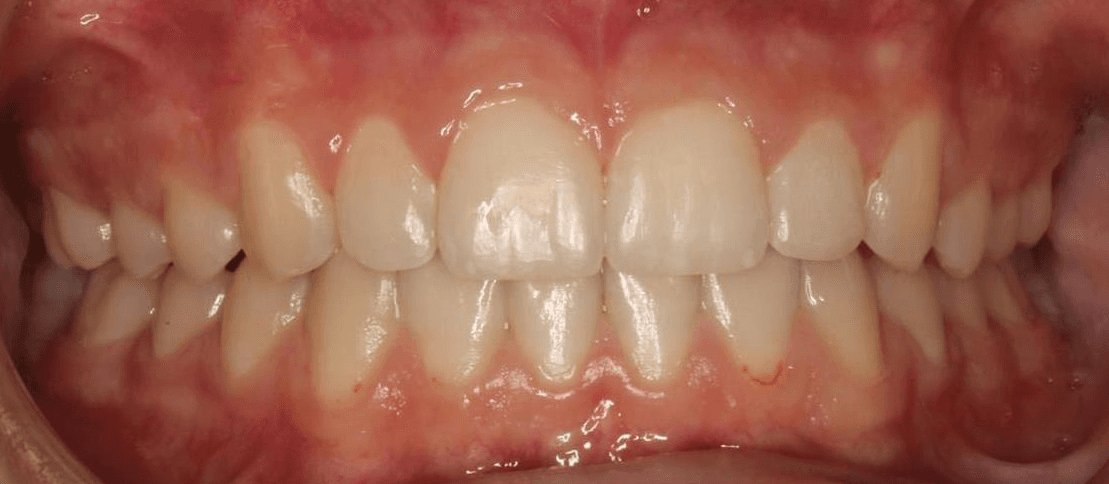

Final results

INTRAORAL